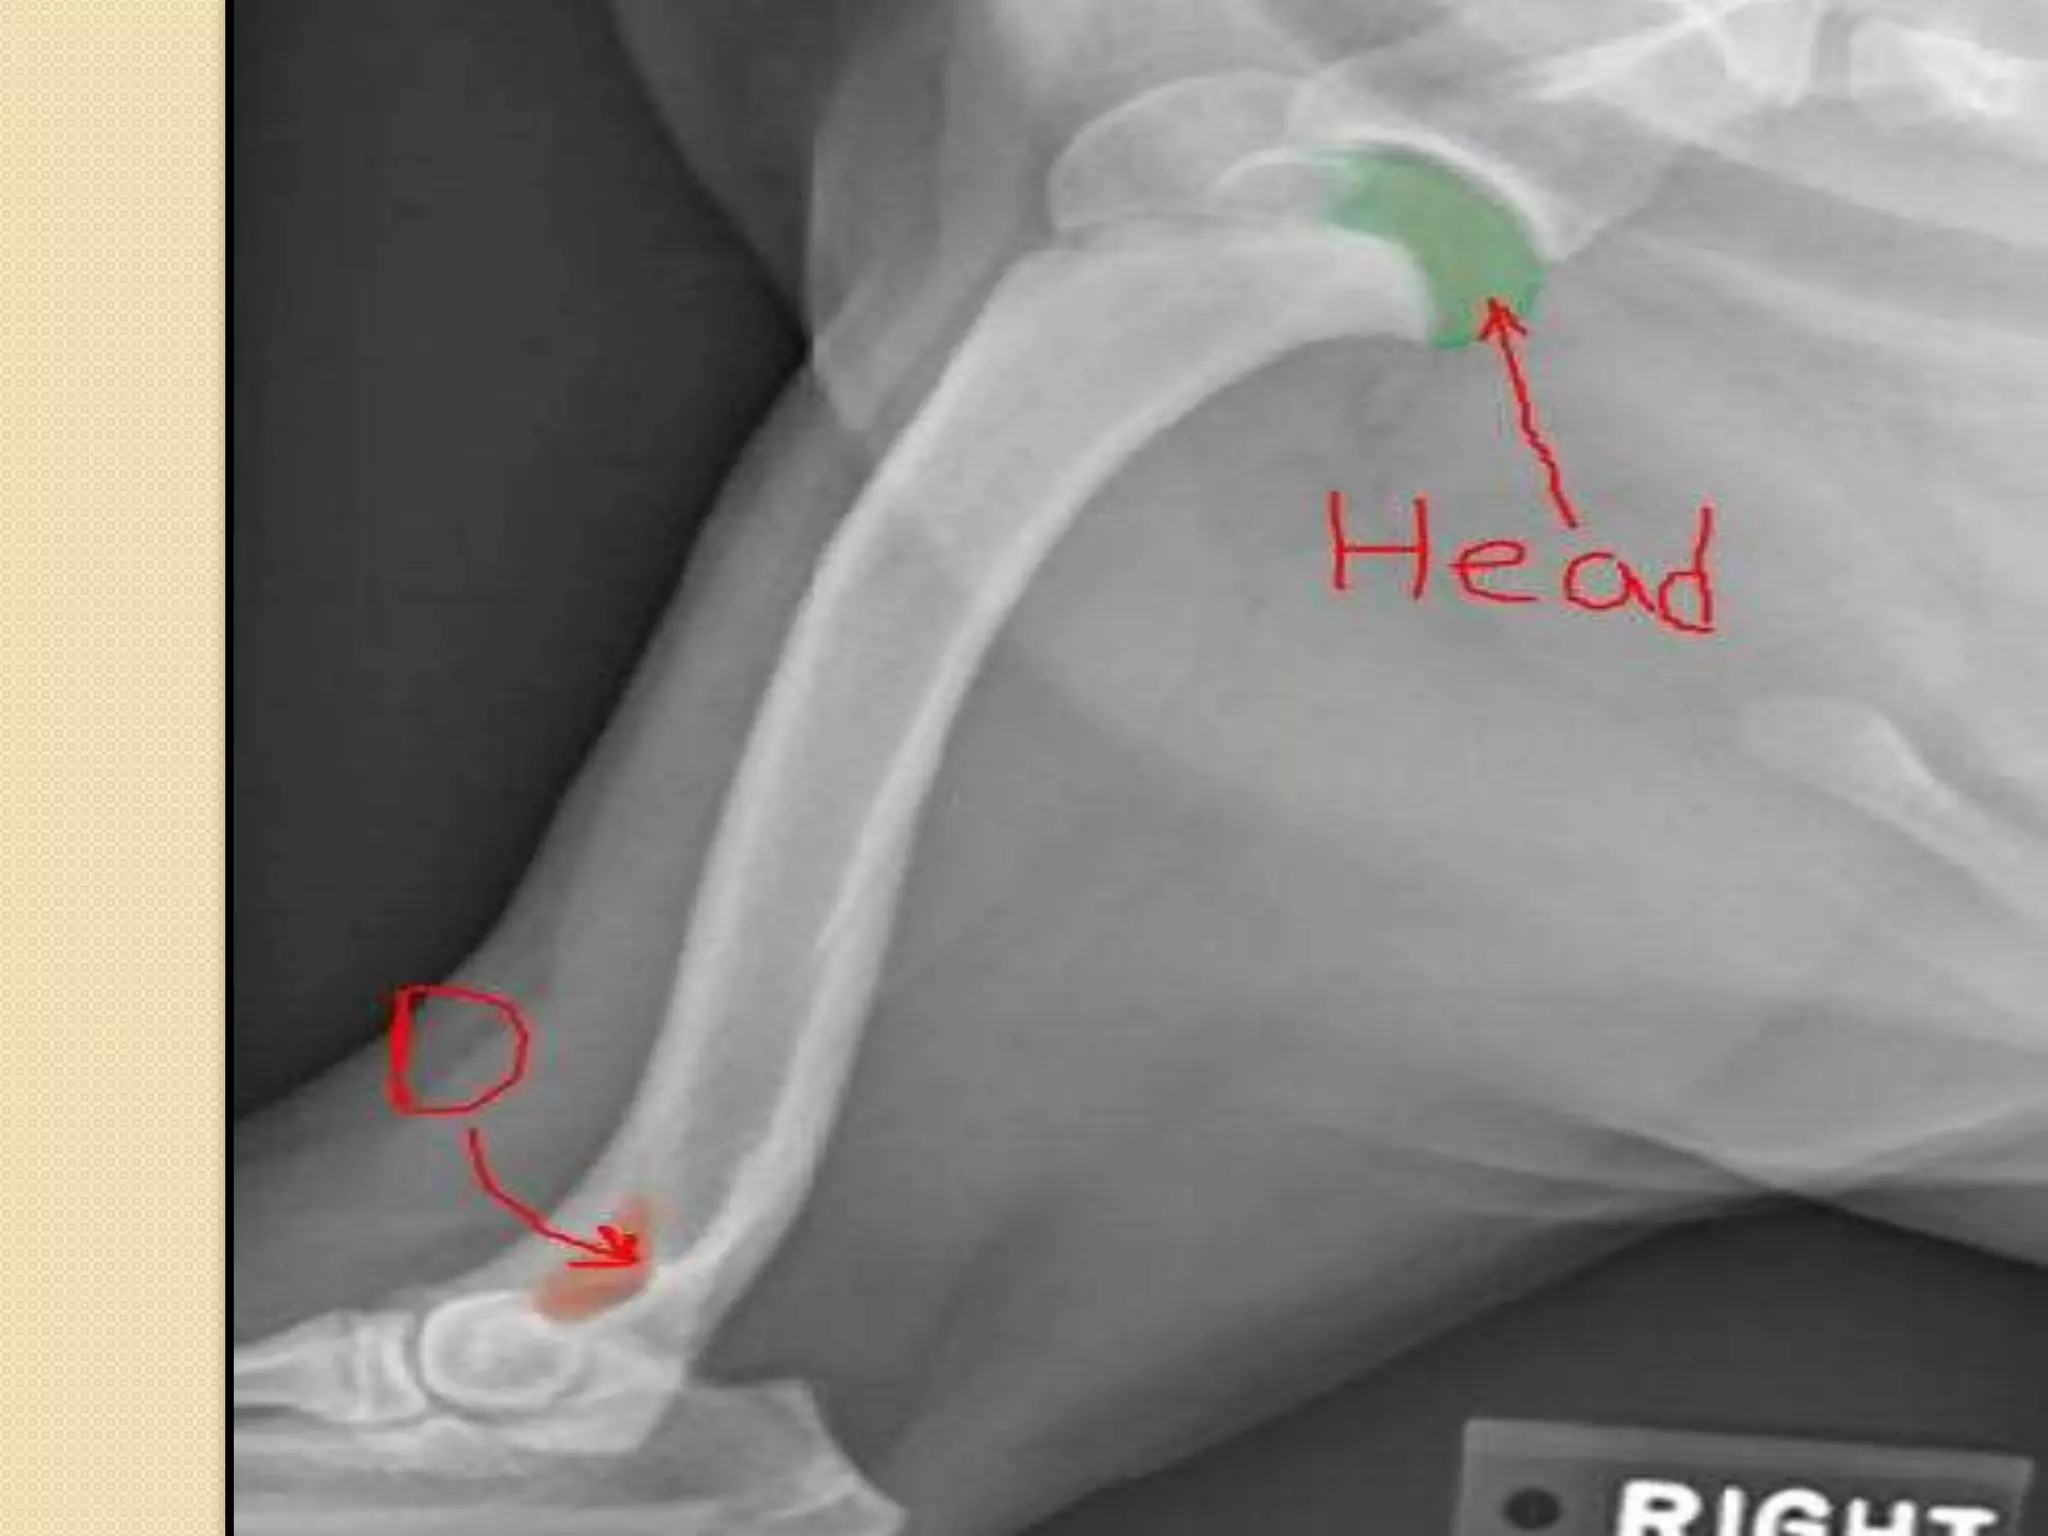

Humerus:

-It is a long bone which is called also the brachium-The head of the humerus with the glenoid cavity

of the scapula form the shoulder joint.

-The presence of supratrochlear foramen

D=supratrochlear foramen

Shoulder joint: